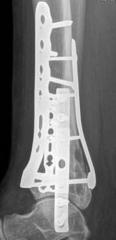

Fig 2.2-6a–b Immediate postoperative x-rays showing restoration of the ankle mortise and distal tibia alignment through anatomical and stable fracture fixation.

1. AP view.

2. Lateral view.